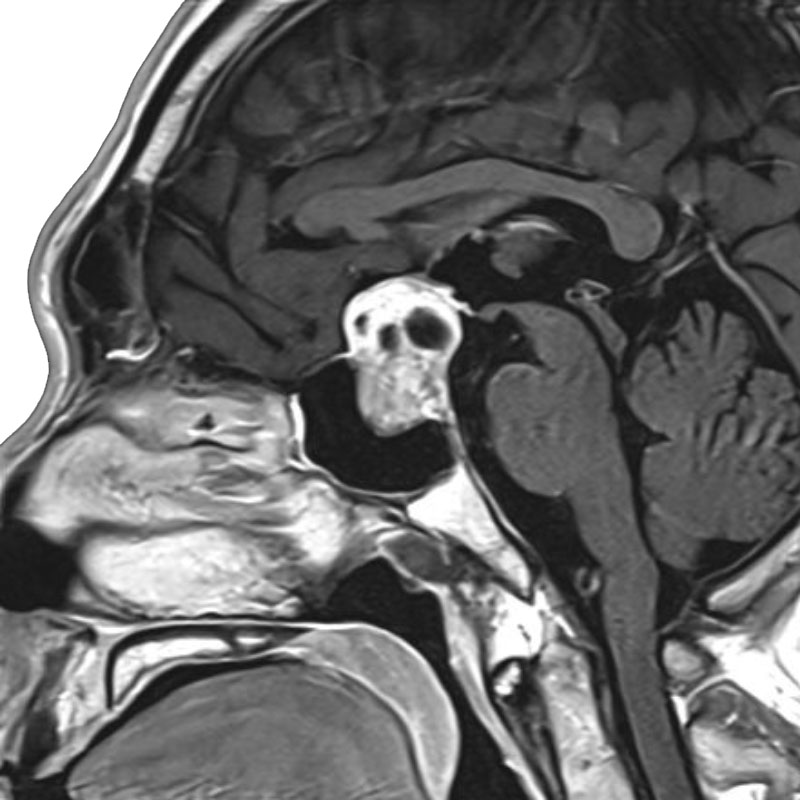

脳室内腫瘍

摘出術

北野/濵田